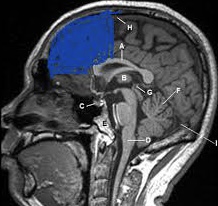

The orange/yellow is where white children have more matter, the blue is where black children have more matter. The Insula is the blue part, mainly responsible for emotions. This is WITH controlling for upbringing.

The orbitofrontal cortex (OFC) is a prefrontal cortex region in the frontal lobes of the brain which is involved in the cognitive process of decision-making

The first study you posted showed that black people have a larger orbitofrontal cortex, which is coloured in orange..?\![]()

The first study I posted measured only 1 area of the frontal cortex which was bigger, not the entire frontal cortex which is colored in orange.